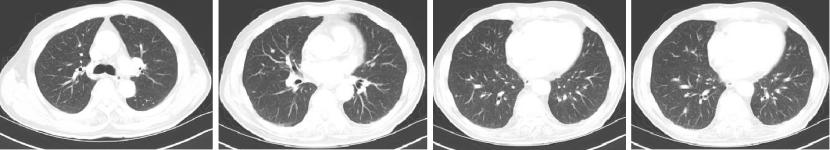

2022-06-12

肺无法穿刺活检。

2022-06-20:西妥昔单抗联合FOLFIRI方案治疗(西妥昔单抗900mg d1,伊立替康320mg d1,氟尿嘧啶0.7g iv 4.3g civ)。

2022-07-06:骨髓抑制、腹泻,西妥昔单抗联合FOLFIRI方案治疗(西妥昔单抗900mg d1,伊立替康280mg d1,氟尿嘧啶0.7g iv 4.3g civ)。

疗效对比:

给予贝伐珠单抗联合TAS-102治疗期间复查CT评估SD,胃肠道反应不重,骨髓抑制Ⅰ度,耐受性尚可。